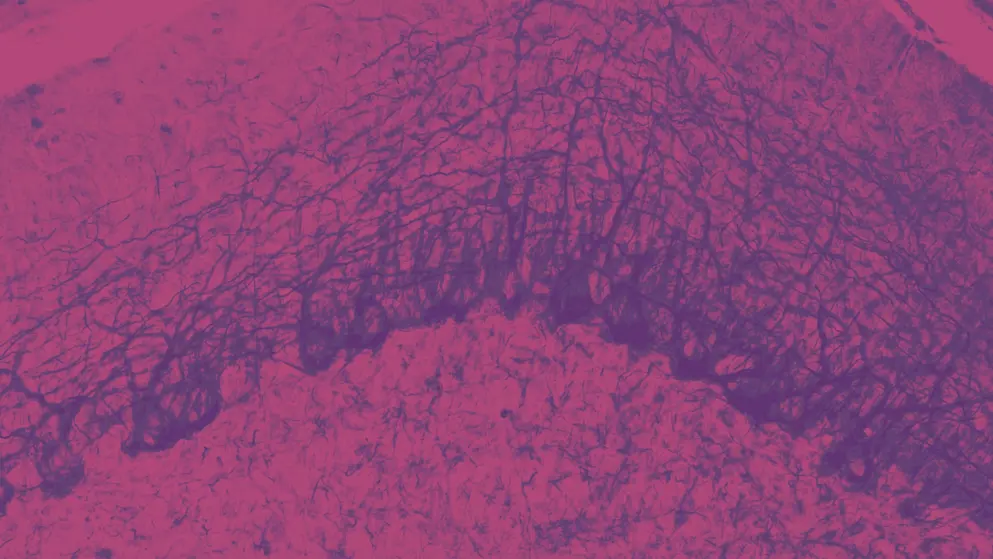

Mounting evidence suggests that migraine pathogenesis recruits the trigeminal nerve and its projections to the intracranial vasculature3. Discovery of signalling molecules involved in migraine pathogenesis led to the development of mechanism-based therapies3, such as anti-calcitonin gene-related peptide (CGRP) monoclonal antibodies and small-molecule antagonists.